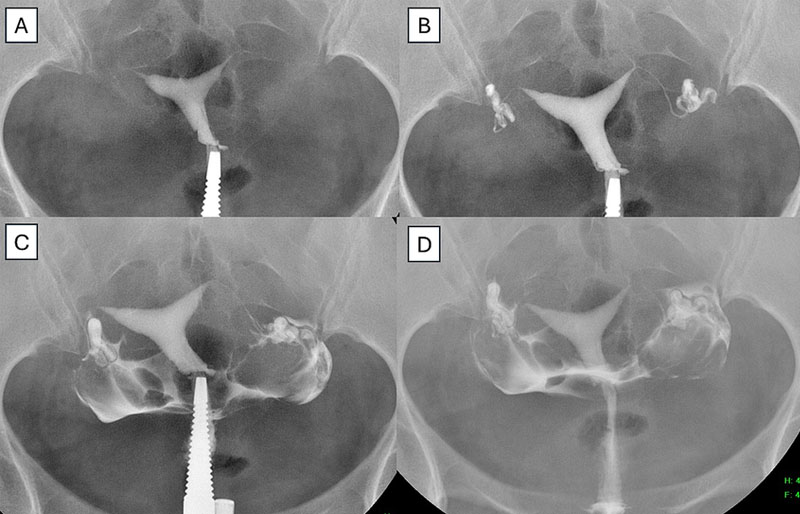

Kỹ thuật chụp tử cung vòi trứng

Chụp tử cung vòi trứng (HSG) là một kỹ thuật chẩn đoán hình ảnh dùng tia X kết hợp với thuốc cản quang để đánh giá hình dạng tử cung và sự thông suốt của vòi trứng. Thủ thuật này giúp phát hiện tắc nghẽn, ứ dịch (hydrosalpinx) hoặc những bất thường ở tử cung như dính, polyp, u xơ, vách ngăn… Từ đó, bác sĩ có thể đánh giá chính xác tình trạng sinh sản và lên kế hoạch điều trị IVF phù hợp.

Thông qua hình ảnh X-quang kết hợp thuốc cản quang, bác sĩ có thể:

- Kiểm tra hình dạng tử cung, phát hiện các bất thường như dính buồng tử cung, vách ngăn tử cung, u xơ tử cung…

- Đánh giá sự thông suốt của vòi trứng, kịp thời phát hiện tình trạng tắc nghẽn hoặc ứ dịch.

Thủ thuật chụp tử cung vòi trứng thường diễn ra nhanh chóng (khoảng 5 – 10 phút) và được tiến hành trong ba giai đoạn chính:

Thực hiện thủ thuật

Một ống thông mảnh được đưa vào buồng tử cung, sau đó thuốc cản quang được bơm nhẹ nhàng để tạo hình ảnh rõ nét trên X-quang.

Bác sĩ sẽ bơm một lượng nhỏ thuốc cản quang vào tử cung qua cổ tử cung, sau đó chụp X-quang để quan sát dòng chảy của thuốc qua vòi trứng.